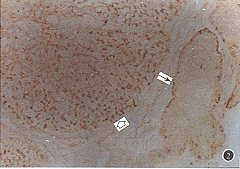

P53蛋白阳性显色为棕色,呈弥漫性或局灶性分布, 定位于肿瘤细胞核内(图1);胞质及肿瘤间质均呈阴性反应。有角化株的SCC,阳性细胞位于癌巢边缘分化较差的细胞中,而中央分化较好的癌细胞为阴性。BCC 组织内阳性细胞数较少,主要位于癌巢周围,染色相对较弱。PCNA阳性反应定位于细胞核内,呈棕色颗粒状。不同组织类型的肿瘤细胞其阳性显色密度及分布状态有差异,同一张切片的不同区域,其细胞阳性显色也不同,具有异质性。肿瘤邻近正常表皮的基底细胞层可见散在的阳性反应细胞,其它非肿瘤组织均未见阳性反应。

图1 P53蛋白在睑板腺癌中的表达,P53蛋白阳性显色呈棕色,位于肿瘤细胞核内(箭头示) ×400